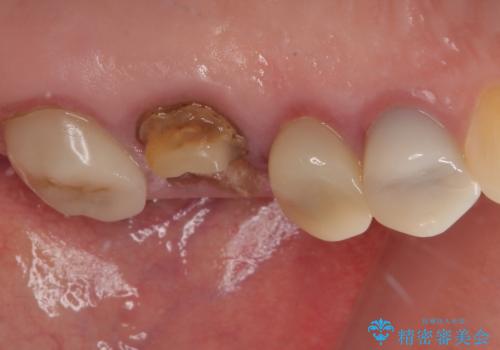

- 奥歯のクラウンが土台ごと外れてしまったとのことで来院された患者様です。

保存可能ではありましたが、予後不良と患者様ご自身が判断されており、相談の結果抜歯即時埋入インプラントによる補綴治療を行うこととしました。

垂直方向への炎症が大きく、抜歯即時埋入はできたものの、即時荷重(インプラント埋入時の仮歯の装着)を可能とする安定値は得られませんでした。